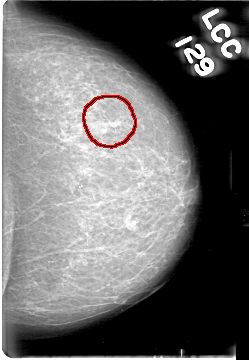

D_4055_1.LEFT_CC

LEFT_CC LINES 5386 PIXELS_PER_LINE 3721 BITS_PER_PIXEL 12 RESOLUTION 43.5 OVERLAY

FILE: D_4055_1.LEFT_CC.OVERLAY

TOTAL_ABNORMALITIES 1

ABNORMALITY 1

LESION_TYPE MASS SHAPE IRREGULAR MARGINS ILL_DEFINED

ASSESSMENT 0

SUBTLETY 3

PATHOLOGY BENIGN

TOTAL_OUTLINES 1

BOUNDARY